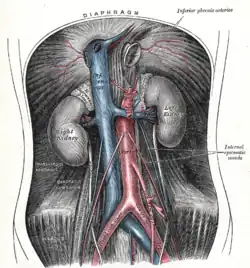

Nierenhilus und Leitungsbahnen

Am Nierenstiel oder Nierenhilus (Hilus renalis) verzweigen sich von ventral nach dorsal Vena renalis, Arteria renalis und der Ureter sowie einige Lymphgefäße und Nerven. Der Hilus erweitert sich im Inneren der Niere in den Sinus renalis, der vom Nierenbecken (Harnwege) und Fettgewebe ausgefüllt wird.

Jede Niere wird von meist einer (sehr selten mehreren) direkt aus der Aorta entspringenden Arteria renalis mit Blut versorgt. Die A. renalis zweigt von der Aorta beiderseits in Höhe der Arteria mesenterica superior ab, zeigt abwärts und teilt sich bereits vor dem Hilum in einen vorderen und hinteren Hauptstamm (Ramus anterior et posterior), die nach ihrer Lage zum Nierenbecken benannt sind und die Segmentarterien abgeben:

Aus dem vorderen Hauptstamm entspringen vor dem Hilus vier Segmentarterien, die A. segmenti superioris, A. segmenti anterioris superioris, A. segmenti anterioris inferioris, A. segmenti inferioris. Der hintere Hauptstamm gibt eine A. segmenti posterioris ab und versorgt nur ein Segment an der Rückseite der Niere. Auf die Arteriae segmentorum folgen die Arteriae interlobares, darauf die Arteriae arcuatae, darauf die Arteriae interlobulares (auch Arteriae corticales radiatae), die schließlich die Vasa afferentia für die Nierenkörperchen der Nephrone abgeben. Zur genaueren Beschreibung der arteriellen Versorgung siehe den Abschnitt Feinbau und den Artikel Nephron.

Die Nierenarterie und jeder ihrer Endäste sind Endarterien, es liegen keine Anastomosen vor, sodass der Verschluss eines Astes jeweils zum Absterben des von ihm versorgten Nierengewebes führt (Nekrose, Niereninfarkt).

Die Vena renalis führt das Blut unmittelbar in die Vena cava inferior. Im Körper liegt die Aorta links, die Vena cava inferior rechts, weshalb die linke Vena renalis länger ist als die rechte. Sie liegt vor der Aorta, unter dem Abgang der Arteria mesenterica superior (→ Nussknacker-Syndrom) und nimmt die V. testicularis bzw. ovarica sinistra auf.